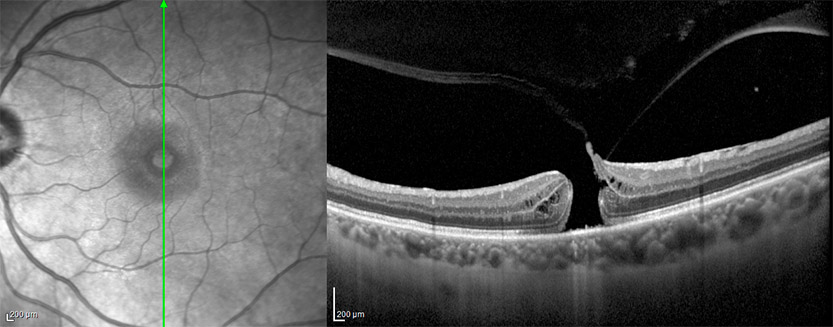

→ Tomografía de Coherencia Óptica u OCT Macular: con esta prueba determinamos el tamaño y la forma del agujero macular para observar el estado de las diferentes capas de la retina y descartar edema macular quístico.

→ Tomografia de coherencia óptica OCT de agujero macular completo.

Como seguimiento, durante el postoperatprio se realiza de nuevo otra prueba por Tomografía de Coherencia Óptica (OCT) para confirmar el cierre del agujero macular.